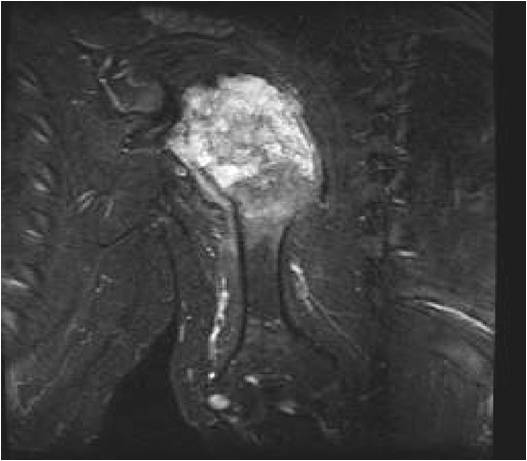

- MRI

- Lobulated margin

- Marked increased intensity long TR images

- Calcified chondroid – low intensity all sequences

MRI:

- Lobulated margin (Lobular Growth Pattern)

- T1 Weighted Images: Intermediate Signal Intensity

- Calcifications will be low signal

- T2 Weighted Images: High Signal Intensity

- High water content shows as high signal on T2 weighted images

- Calcifications will be low signal

- Marked increased intensity long TR images

- Calcified chondroid – low intensity all sequences

- There should never be any cortical destruction nor a soft tissue component. If this exists then the tumor must be a chondrosarcoma.

- Endosteal scalloping and cortical expansion is acceptable for phalangeal tumors. In most benign long bone cartilage tumors there is minimal endosteal scalloping but there should be no cortical expansion nor thickening. There should be no cortical destruction and no soft tissue component associated with an enchondroma. Cortical destruction, periosteal thickening, cortical expansion and a soft tissue component indicates a chondrosarcoma of the long bone.